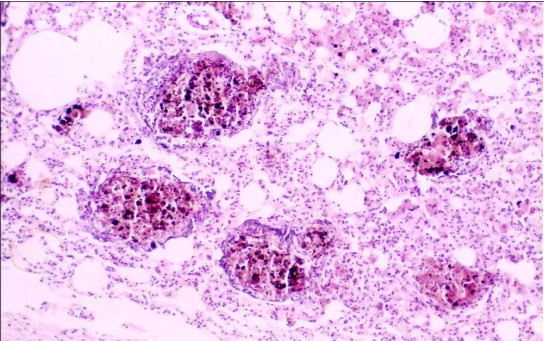

显微成像技术在职业卫生观测中的挑战

在常见职业病的检测中,如尘肺病的检测及重金属中毒的检测,需要用到高倍的显微镜进行观察,在评估检测的过程中,要对细胞的形态进行对比分析,便要求了更高的成像效果,这既是对显微镜有更高的要求,也是对显微相机有着更高的要求,以便能更好的评估细胞的形态并对此分析。